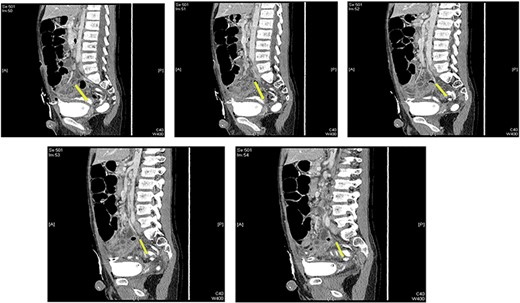

Laboratory investigations showed following results: white blood cell count 24.00 × 103/μl (reference range 4.5–11), hemoglobin 13.6 g/dl (reference range 13–16), C-reactive protein 76.5 (<5 nl). A computed tomography (CT) scan of the abdomen and pelvis using oral and intravenous contrast showed a distended appendix filled with fluids (Fig. 1). Also observed were pockets of air with a larger proximal and smaller distal fecolith with free fluid in Morison’s pouch, right paracolic gutter and rectovesical pouch consistent with acute complicated appendicitis.

Preoperative CT scan (axial section) showing a dilated appendix with an enhanced wall filled with fluids and air pockets (A). A large appendicolith was noted. The coronal section shows a dilated appendix with an enhanced wall filled with fluids and air pockets. A large appendicolith was noted (B).